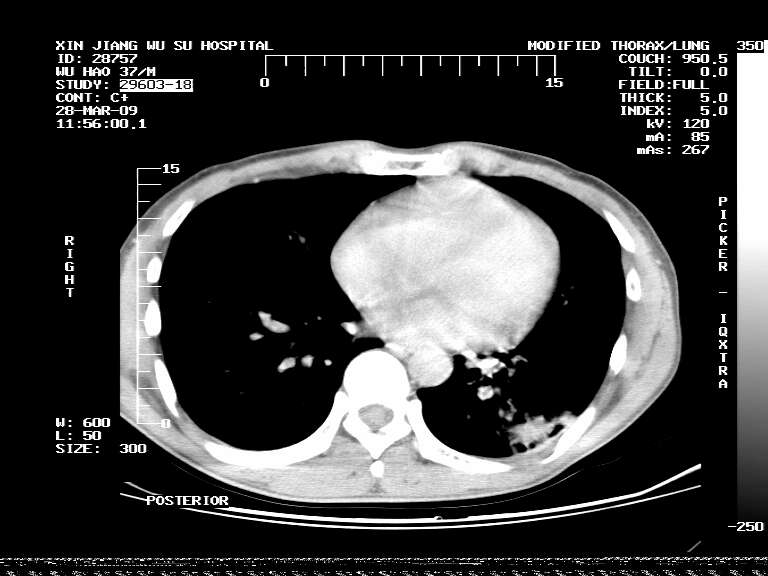

男,37岁,体检胸透发现阴影。

患者体检发现 无症状 左肺下叶占位,边缘模糊,可见血管聚束、分叶、胸膜牵拉,增强呈不均匀性强化。 首先考虑左肺下叶周围型肺癌,建议穿刺活检。

左肺下叶见一结节病变,边缘欠清不光滑,与胸膜粘连且胸膜局限性增厚,注药后呈环形强化,动脉期壁呈明显点环状强化,静脉期壁强化减低,中心密度低无强化,灶周无明显的卫星灶和水肿区(晕征)---考虑周围性肺癌,不除外感染性病变,建议穿刺活检。

左肺下叶软组织病灶,密度较高,内见点状钙化,其周围见子灶,邻近胸膜扁平样增厚.c+病灶强化明显,中心强化弱.诊断:左肺下叶结核瘤.

左肺下叶大片实变影,内靠胸膜见不规则更高密度结节灶,边缘强化,相邻胸膜增厚,胸膜下脂肪线存在。考虑炎症,结核可能。